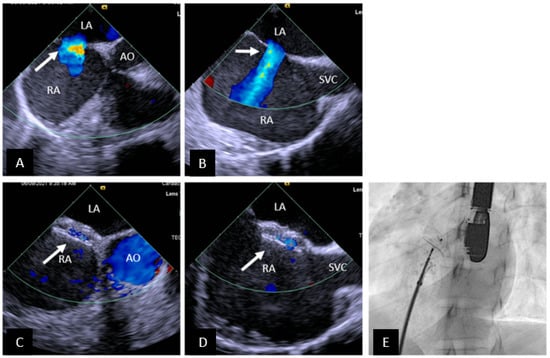

- Batteux, C.; Meliani, A.; Brenot, P.; Hascoet, S. Multimodality fusion imaging to guide percutaneous sinus venosus atrial septal defect closure. Eur. Heart J. 2020, 41, 4444–4445. [Google Scholar] [CrossRef]